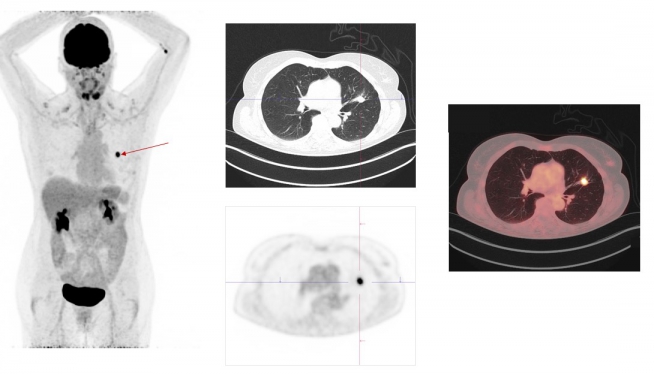

Case study Oncology: